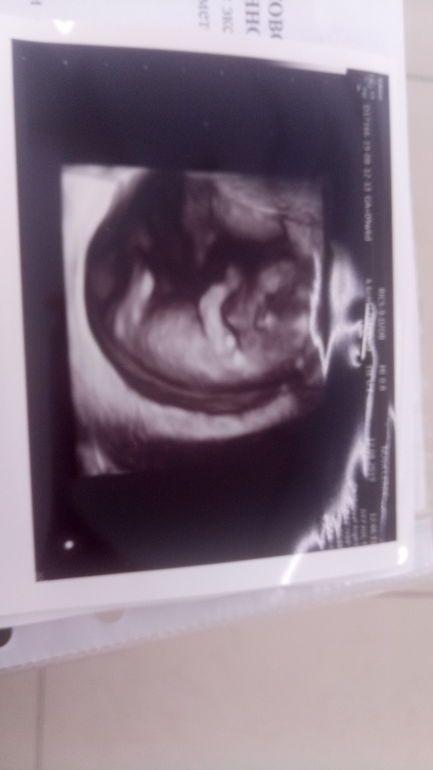

Это прекрасно, поздравляю! Желаю успехов и дальше! Сейчас вспомнила этот срок и нашла УЗИ, которое делала как раз на таком срок, только там 9недель и 6 дней было. Уже прям очень похож на человека. Изображение

Elvirochka, ого.. У меня по скромнее узи)) но уже видно человечка))

Александра Гаврилова, это в Новаклиник получилось так заснять. Удачный кадр, дочь и сейчас очень фотогеничная😁

Elvirochka, вот это красотка 💕 Хочется тоже такой снимок) Это обычное УЗИ так зафиксировало?

Полина , спасибо! да, было самое обычно УЗИ первого триместра.